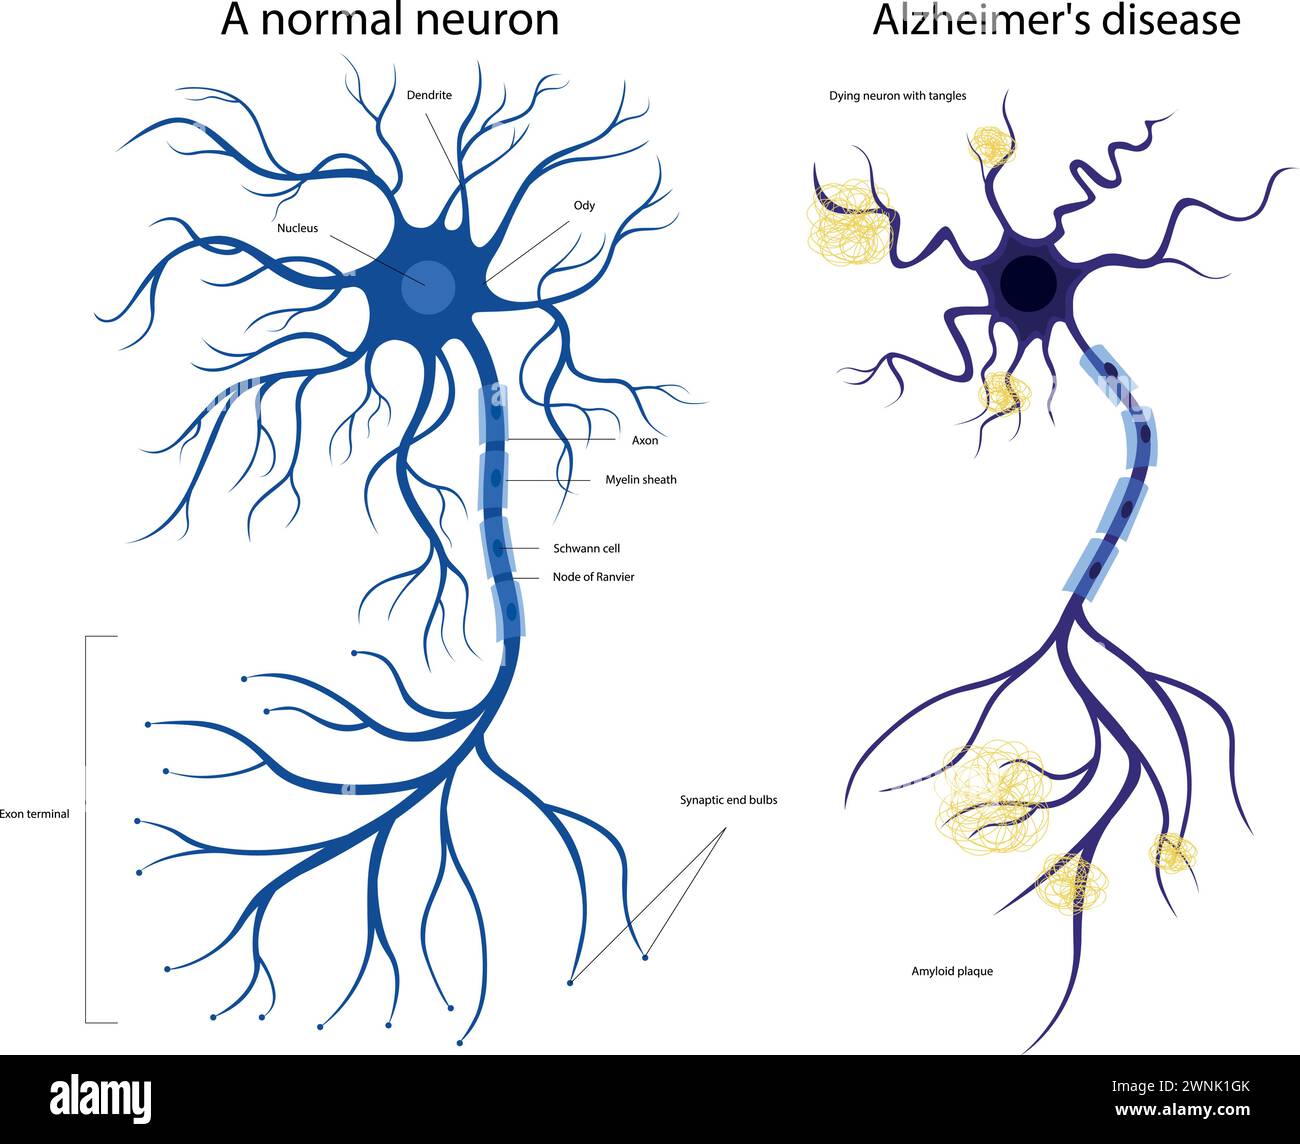

RF2WNK1GK–La struttura di un neurone malato e sano. Neurone danneggiato. Malattia di Alzheimer. Malattia cerebrale demenza, disturbi della memoria. Un neurone nell'Alzheimer